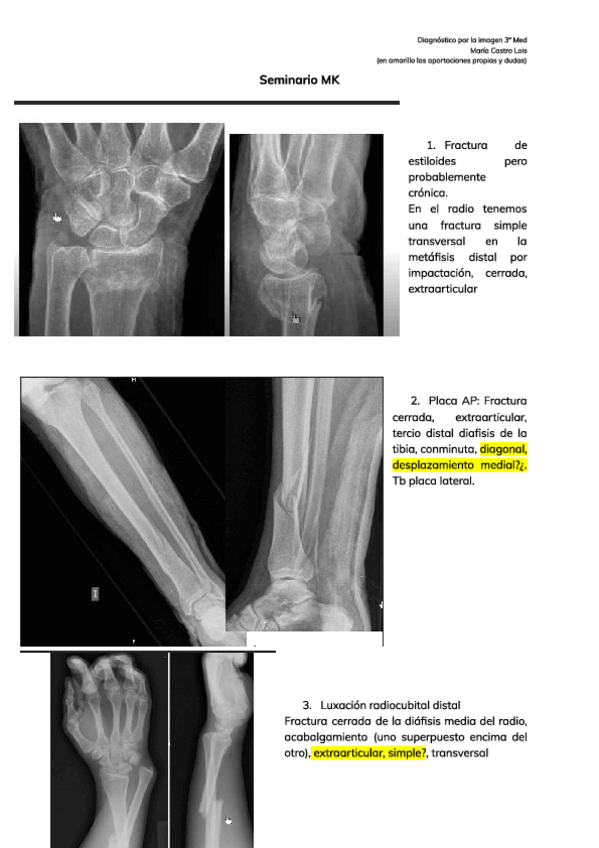

He publicado nuevos apuntes de 3º Introducción a la Cirugía, Medicina preoperatoria: seminario-MK.pdf

17 páginas